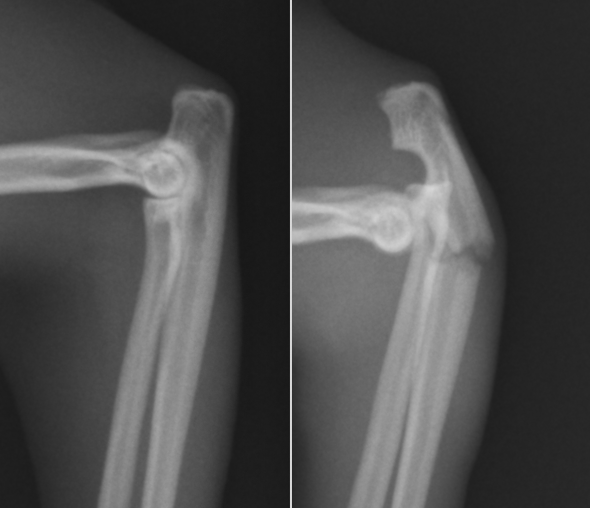

横から撮影したX線の拡大です。左が正常の骨で、右が骨折した骨です。